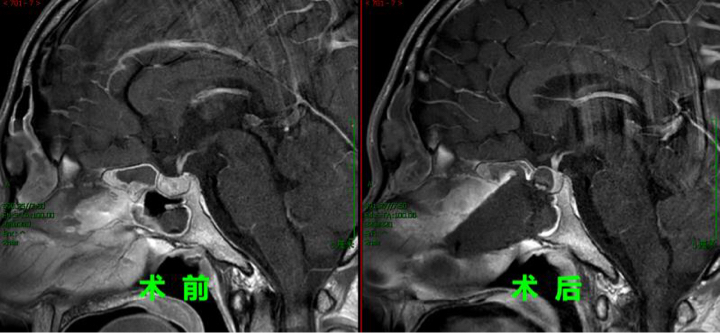

仁济医院垂体疾病多学科团队给予患者小段“一站式”诊疗服务。内分泌科使用药物控制甲亢,待甲状腺功能恢复正常后方可实施手术治疗。患者经济条件不佳,专家团队根据文献报道决定采用便宜的短效针剂,虽然工作量大,但仅仅用十分之一的费用很快就把患者的激素指标控制下来,才短短一个月,病人小段的甲状腺功能五项指标均已控制到正常范围。而且复查垂体磁共振后惊喜得发现,在用药前后,肿瘤已经明显较前缩小了,现在是“万事俱备只欠东风”了。

要彻底治愈该病首选手术切除肿瘤。王宇医生通过详细的术前准备工作,最后经鼻内镜微创手术,将罕见肿瘤“一锅端” 。 手术后病人迅速恢复,所有症状立即消失了,短短几天小段就出院康复。